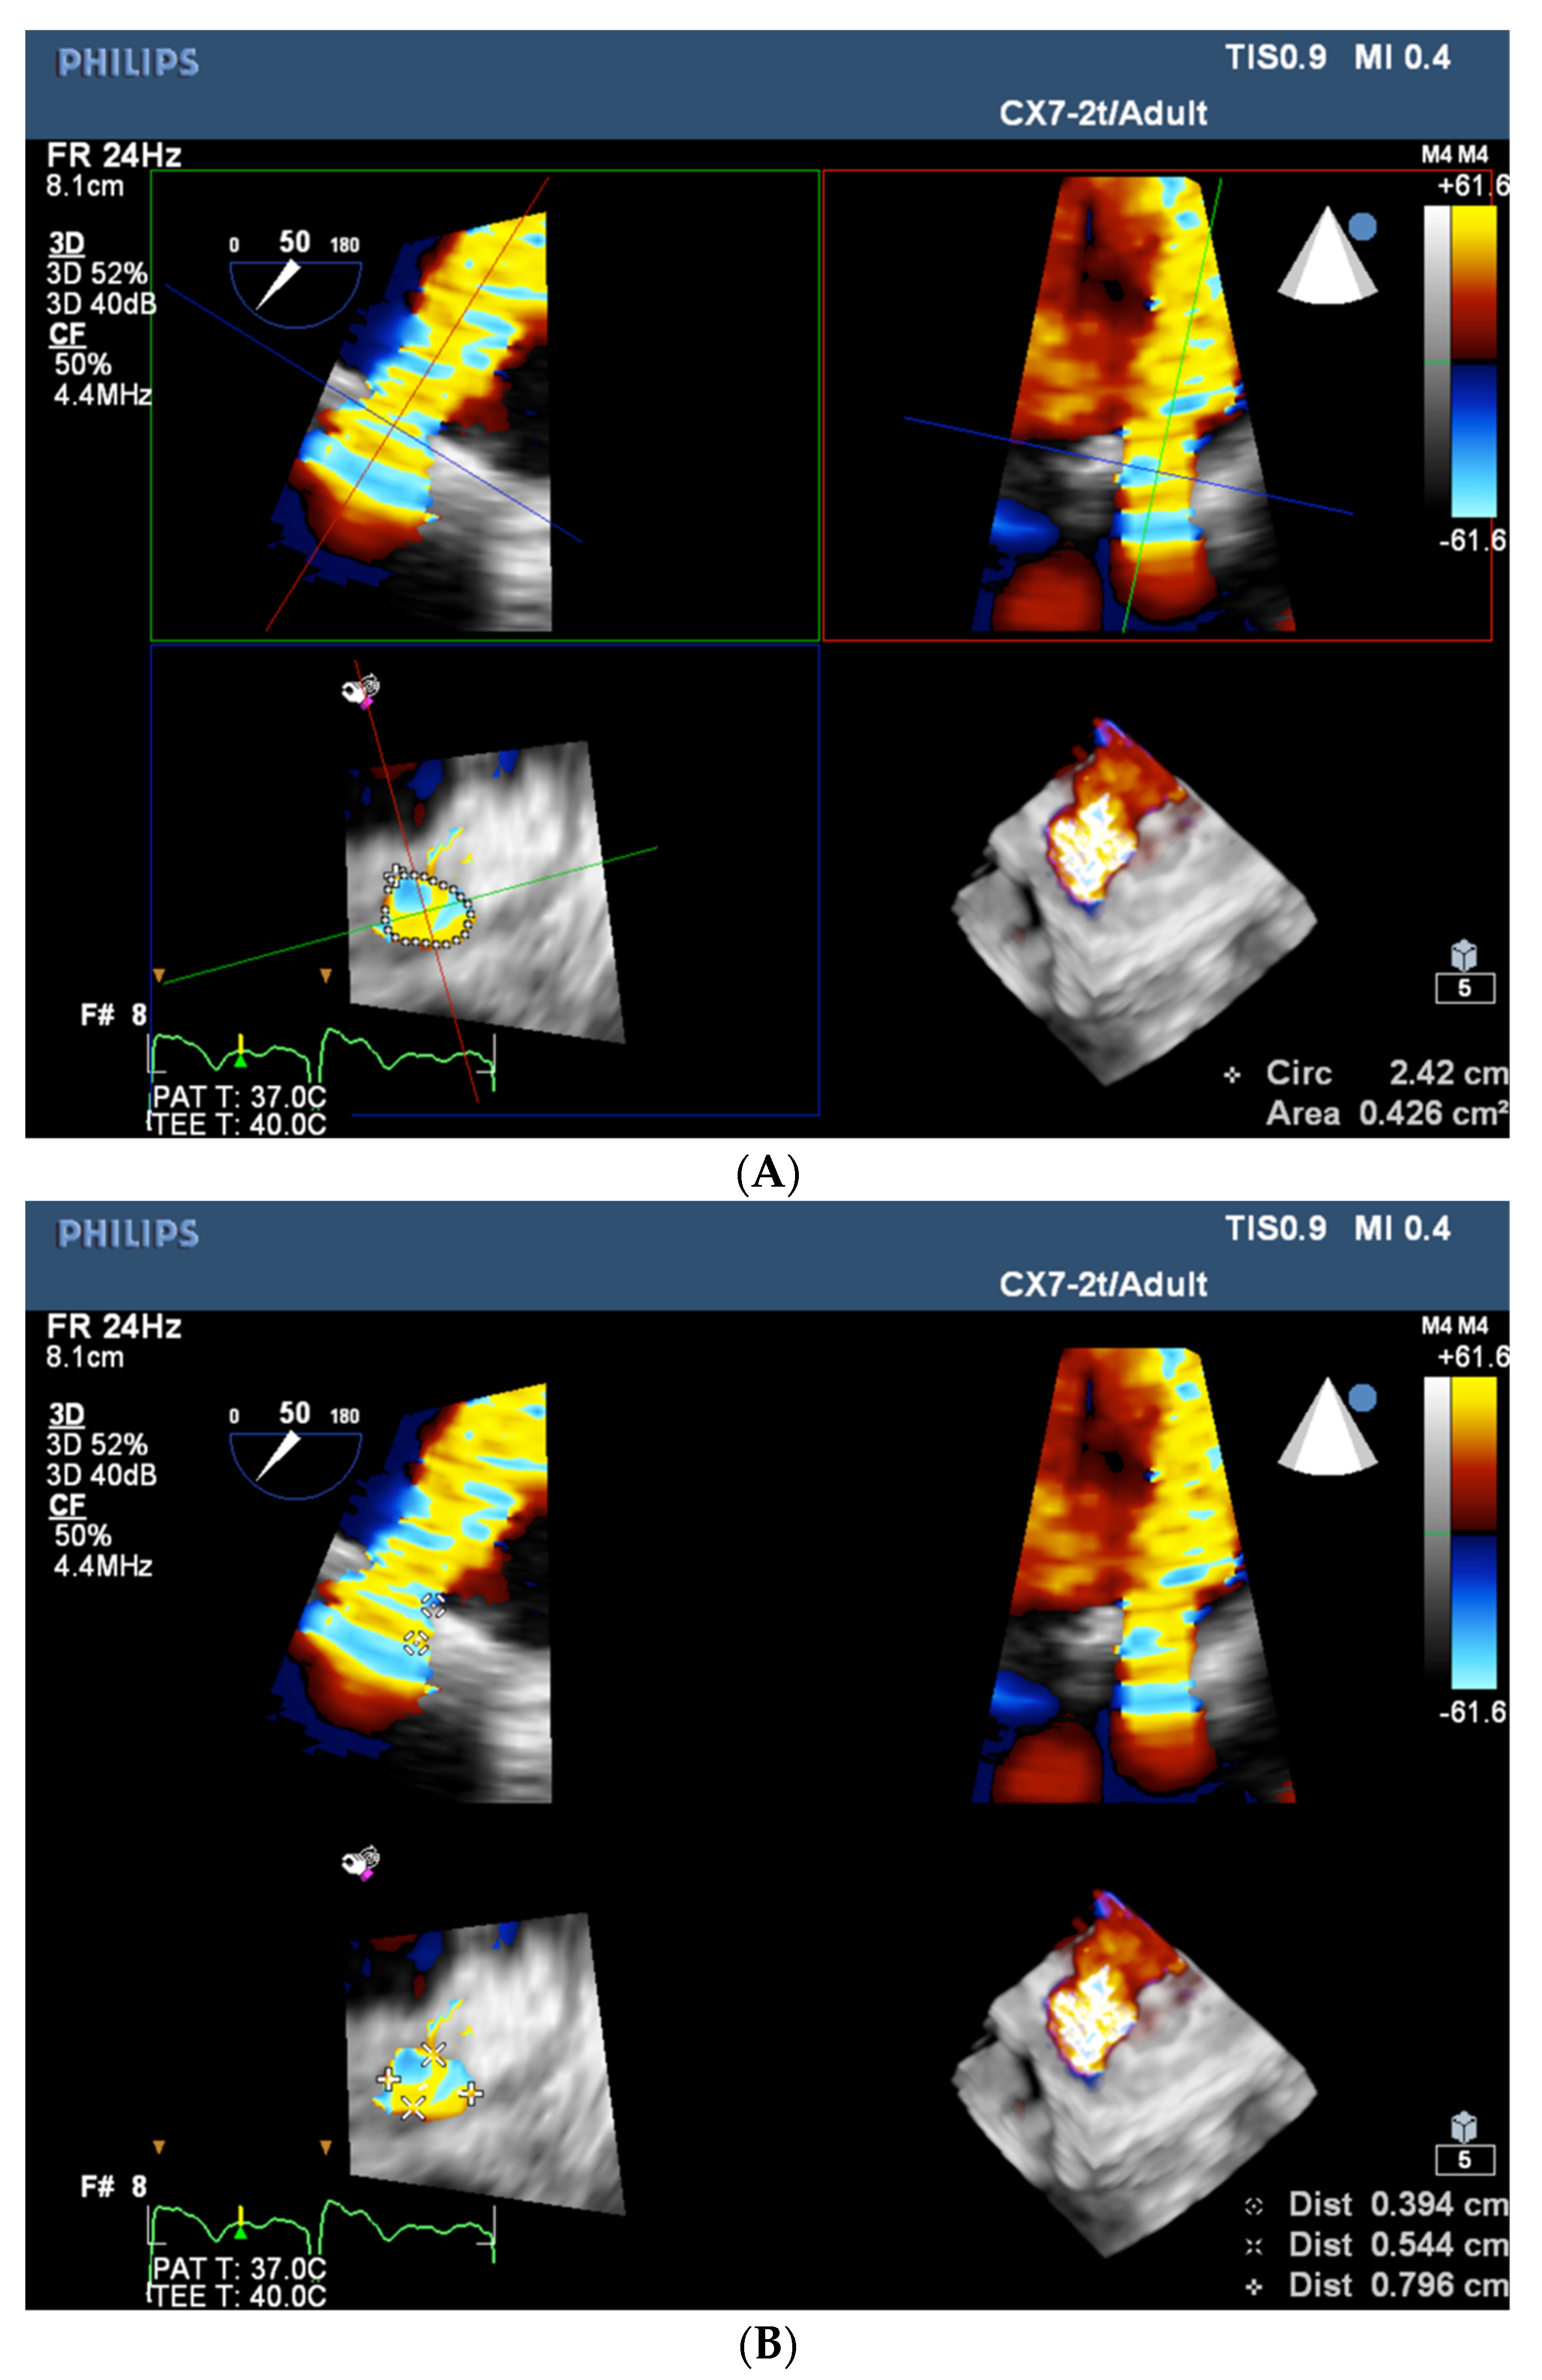

- Pysz, P.; Kozłowski, M.; Malczewska, M.; Adamczyk-Filipek, E.; Wojakowski, W.; Smolka, G. Prospective registry validating the reproducibility of mitral paravalvular leak measurements in a standardized real-time three-dimensional transesophageal echocardiography algorithm for optimal choice of the closure device. Postep. Kardiol. Interwencyjnej 2019, 15, 203–210. [Google Scholar] [CrossRef] [PubMed]